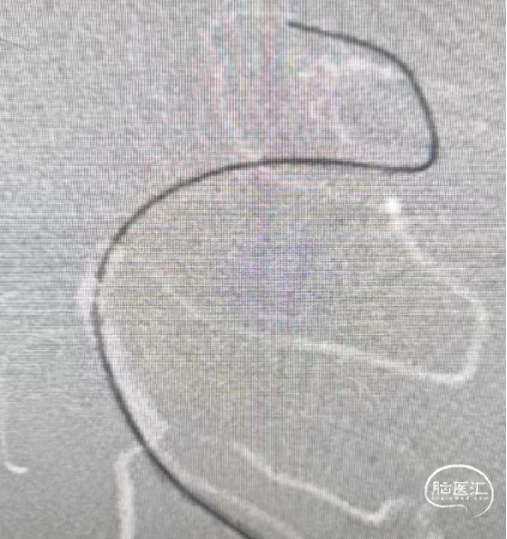

2024.07.11 行急诊介入手术,闭塞情况大致如前:

建立通道,微导管首过效应阳性。

释放6*35mm Syphonet®取栓支架,使用2.0*15mm SacSpeed®球囊扩张导管扩张病变;观察15分钟,血流未能维持;改用2.5*15mm SacSpeed®球囊扩张导管进行扩张。

再次扩张后继续观察,血管弹性回缩明显,支架植入成型。